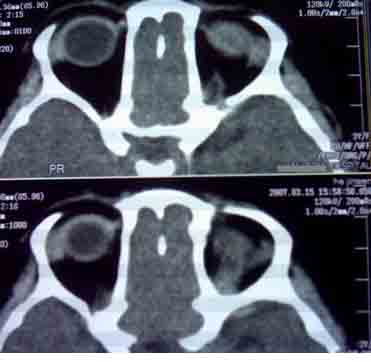

患者,偶然发现左眼无光感,平时,无明显不适,眼外观无明显异常。

首先考虑视网膜母细胞瘤。

支持左侧视网膜母细胞瘤,可惜没有钙化。

大家有没有想到有哪些需同成视网膜细胞瘤鉴别诊断的疾病?正是没有钙化,所以此病首先更应该考虑什么?请大家说说看。

考虑左侧眼球渗出增殖性视网膜炎所致视网膜剥离,建议mri检查。

1.ct表现:眼球内均匀高密度肿块,有增强,并多有点状或团块状钙化,在3岁以下的儿童有极大的诊断价值。可见相关视网膜下积液。

2.mr表现:肿瘤t1加权像为较视网膜略高或与视网膜相等的信号强度,t2加权像为低信号强度。大钙斑t1、t2加权像均为低信号斑,小钙斑不易显示。视网膜下积液或积血显示清楚。

鉴别诊断 :需与渗出性视网膜病鉴别。